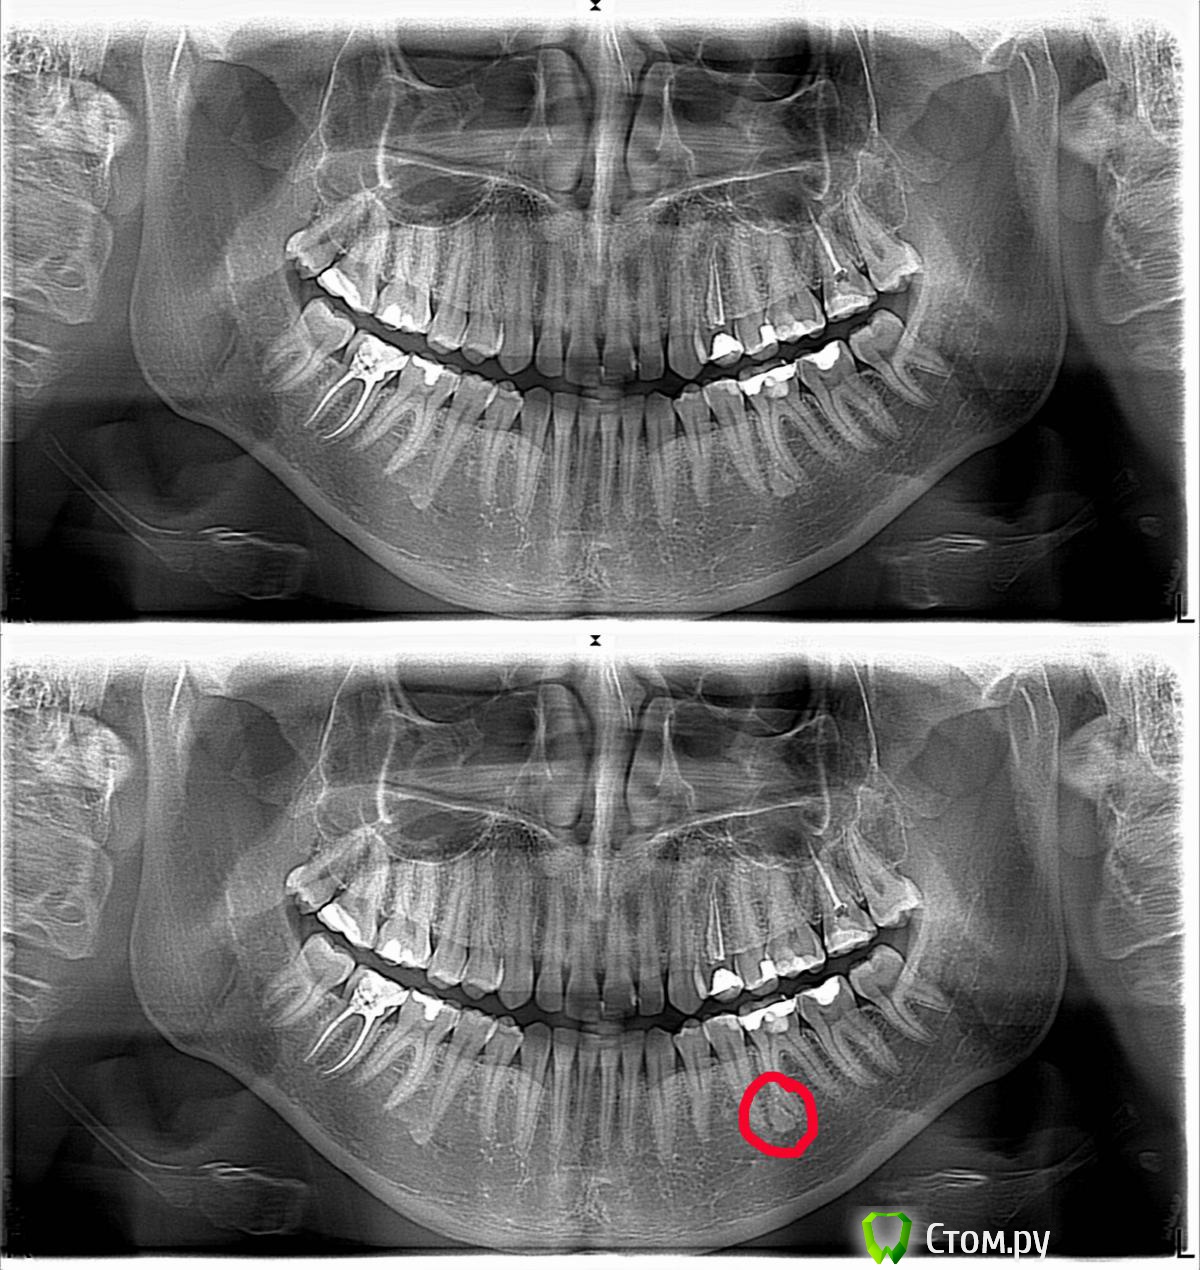

mzza Опубликовано 2 июня, 2014 Поделиться Опубликовано 2 июня, 2014 (изменено) День добрый уважаемые Врачи. Прошу прощения если покажется что расплодил тему ... просто не знаю к хирургии это или к терапии... Сегодня в очередной раз посетил стоматолога. В очередной раз с "фантомной" болью. Зуб и раньше эпизодически реагировал на боль. В 2010 г. был сделан рентген, ничего аномального замечено не было (на тот момент). Сегодня сделал снимок, и при сличении архивного и свежего была выявлена странная белая область... После этого отправили меня делать панарамное фото.Коротко о зубе. Внешне без заметных проблем, реагирует на воздух под давлением. При этом после воздействия боль сразу проходит (не ноит). Больно когда стискиваешь сильно зубы или жуешь активно что-либо... больно от мороженого, ноит только тогда когда застудишь ноги.... ПОВТОРЮСЬ.. как перстаешь воздействовать - боль проходит. Ещё из приятного... прочищая зубной нитью полость между зубами часто выявляется сладковатый гнилистый запах от нити (на остальных зуба такого нет). Вот собственно панорама... Римские развалины Завтра идти показывать снимок... и принимать решение как дальше с зубом поступить...Чтобы не ошибиться с диагнозом и не потерять зуб / жизнь / время / деньги ... подскажите что делать... Жуткий смайлик получился... Изменено 2 июня, 2014 пользователем mzza Ссылка на комментарий

Гарриевич Опубликовано 2 июня, 2014 Поделиться Опубликовано 2 июня, 2014 В том месте, между зубами, застревают микросопиеские остатки пищи, отсюда и запах и привкус. 6 зубе скорее всего периодонтит, а рядом на 5 кариес 1 1 Ссылка на комментарий

DokDent Опубликовано 2 июня, 2014 Поделиться Опубликовано 2 июня, 2014 Ноет когда замёрзнут ноги скорей всего 6-ка, а кратковременные боли возможно даёт 7-й. Белое пятно скорей всего остеомка (ну как бы уплотнение костной ткани). 1 Ссылка на комментарий

shishok Опубликовано 3 июня, 2014 Поделиться Опубликовано 3 июня, 2014 Аналогичное уплотнение и в области верхушки 45 зуба. Ссылка на комментарий

Alexey Doc Опубликовано 3 июня, 2014 Поделиться Опубликовано 3 июня, 2014 Белые области на ваших снимках - очаги остеосклероза. Не требуют лечения 3 Ссылка на комментарий